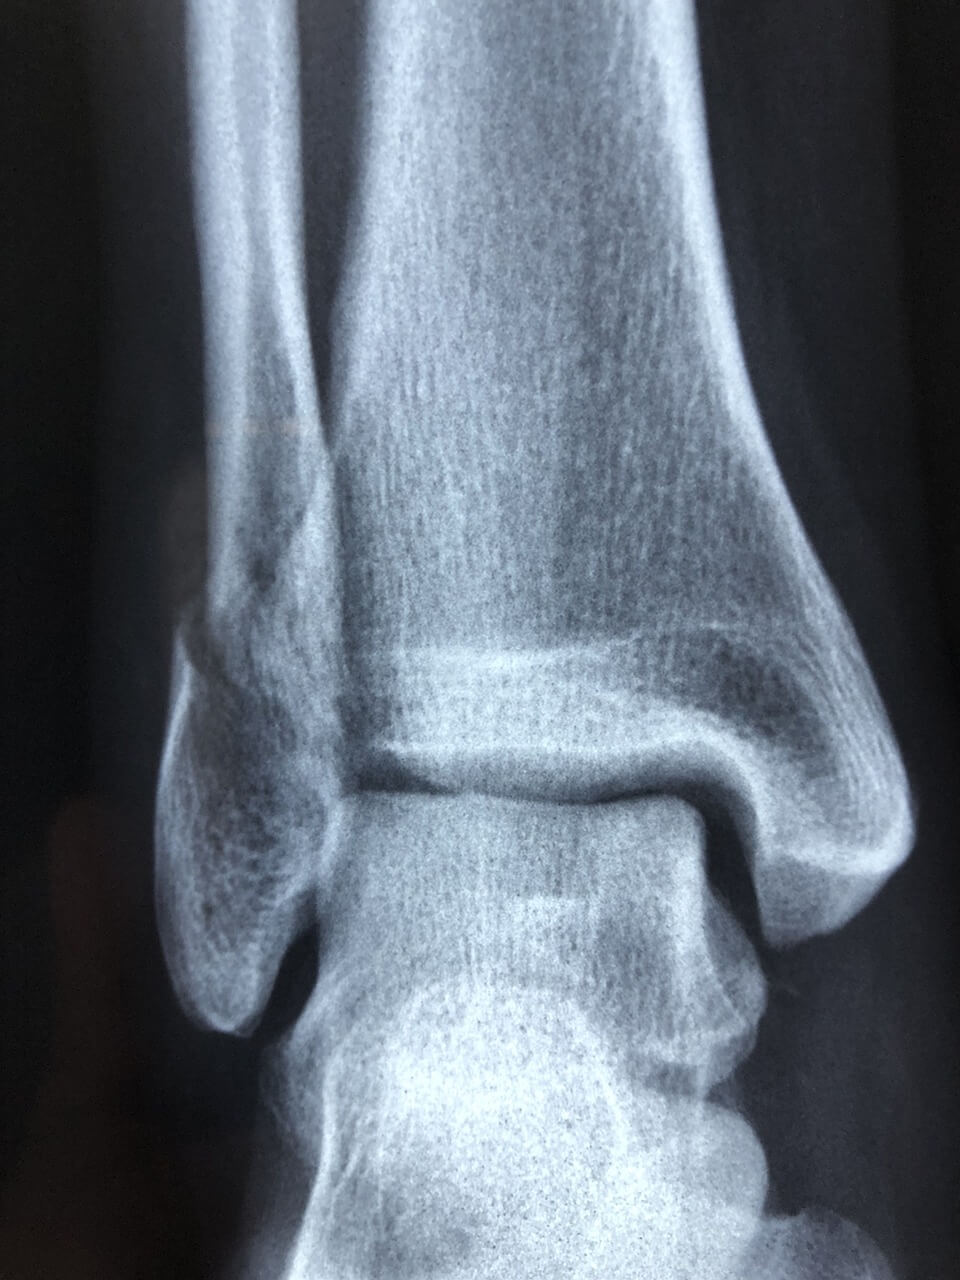

많은 사람들이 발목 염좌와 골절을 혼동합니다. 염좌는 일정 시간이 지나면 보행이 어느 정도 가능하지만, 골절은 체중 부하 자체가 불가능하고 뼈의 모양이 변형될 수 있습니다. 정확한 구분을 위해서는 X-ray나 MRI 검사가 필요합니다.

- X-ray: 골절 여부를 확인하는 기본 검사.